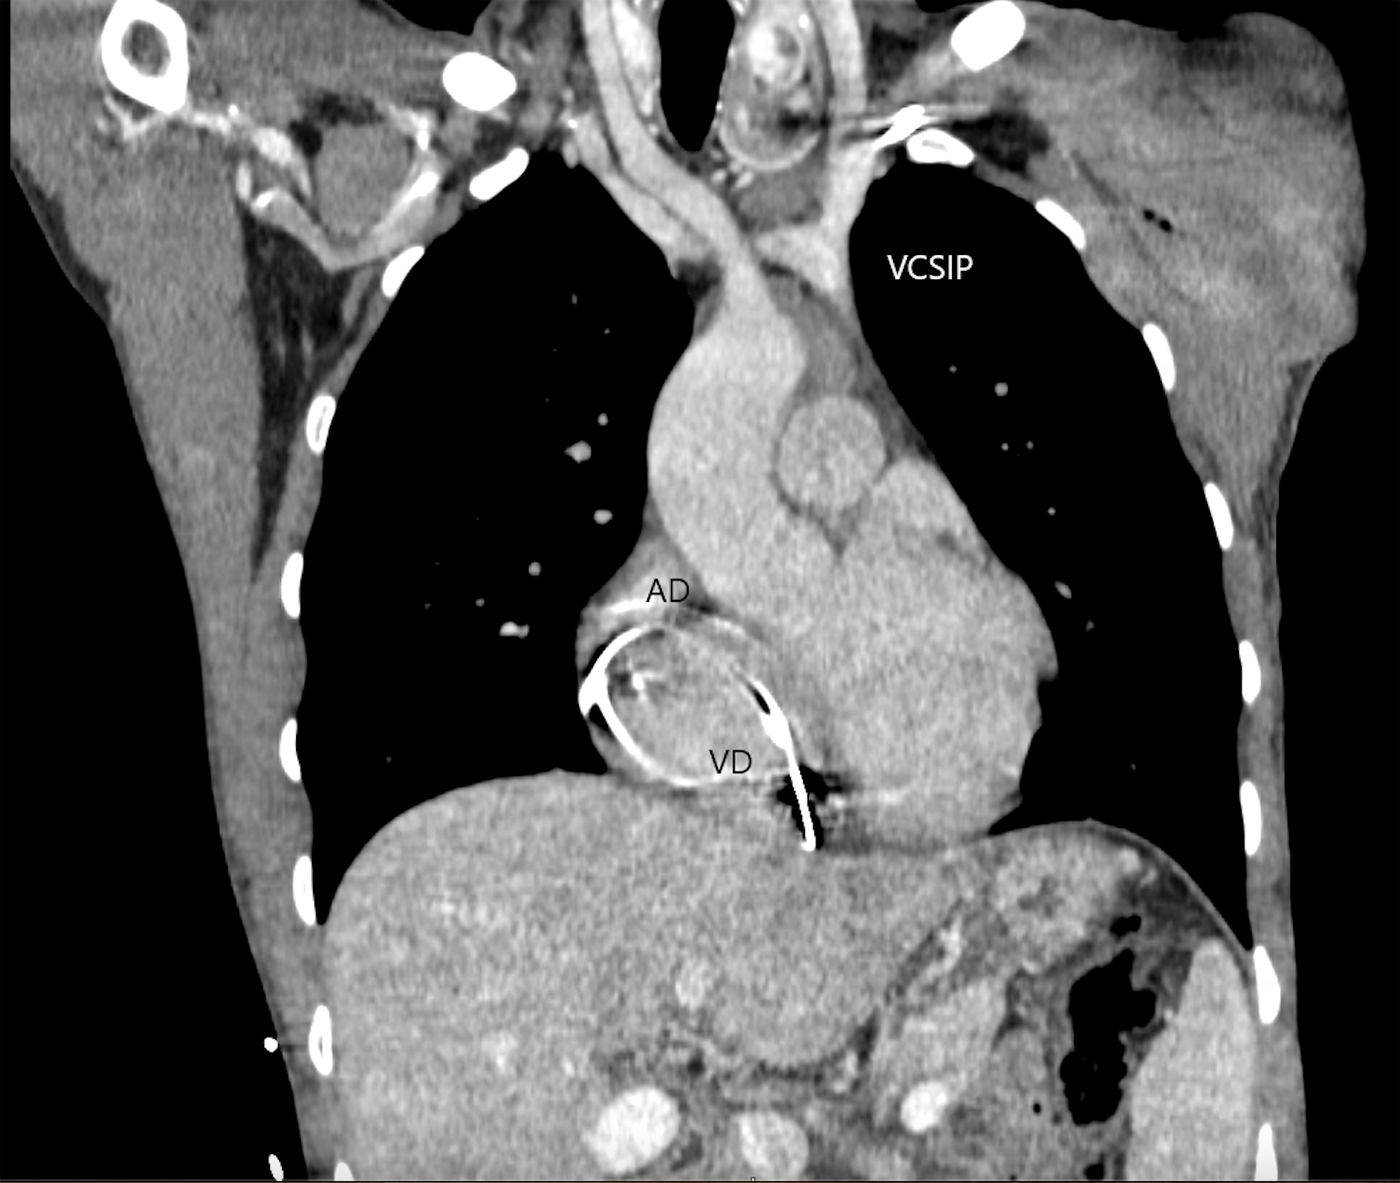

Varón de 31 años con bloqueo bifascicular alternante con bloqueo auriculoventricular completo sintomático con ecocardiograma normal. Se realiza implante de marcapasos definitivo a través de la vena subclavia izquierda, y al introducir la guía metálica se objetiva una vena cava superior izquierda persistente (VCSIP) única, comprobada mediante flebografía y tomografía. La VCSIP desemboca en el seno coronario (SC) y este en la aurícula derecha (AD); se implantaron los electrodos auricular y ventricular derecho (VD) de fijación activa mediante vía retrógrada por el SC (figs. 1 y 2).